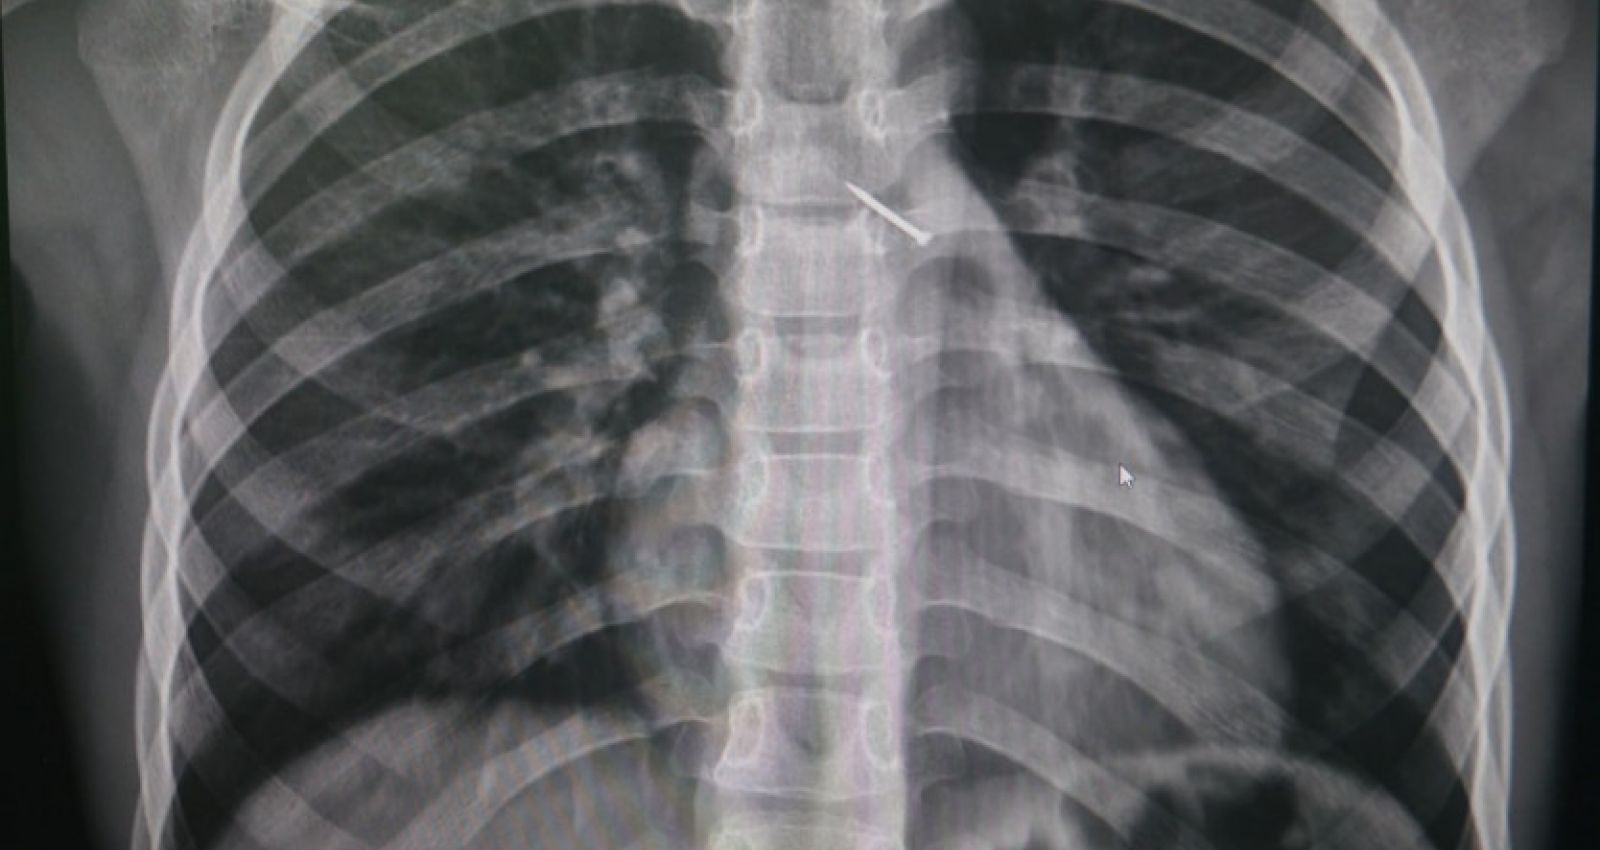

Источник фото:  Министерство здравоохранения Новосибирской области

Выяснилось, что во время активной игры на улице ребенок случайно вдохнул острый предмет. В больницу мальчик поступил с болью за грудиной и невозможностью глубоко вдохнуть. Рентген  показал, что канцелярская кнопка попала в бронхи, уперлась в одну из стенок и вызывала  воспаление.

Медики успешно извлекли опасный предмет при помощи эндоскопических зажимов. После этого юный пациент прошел ингаляционную терапию и был выписан спустя 4  дня.